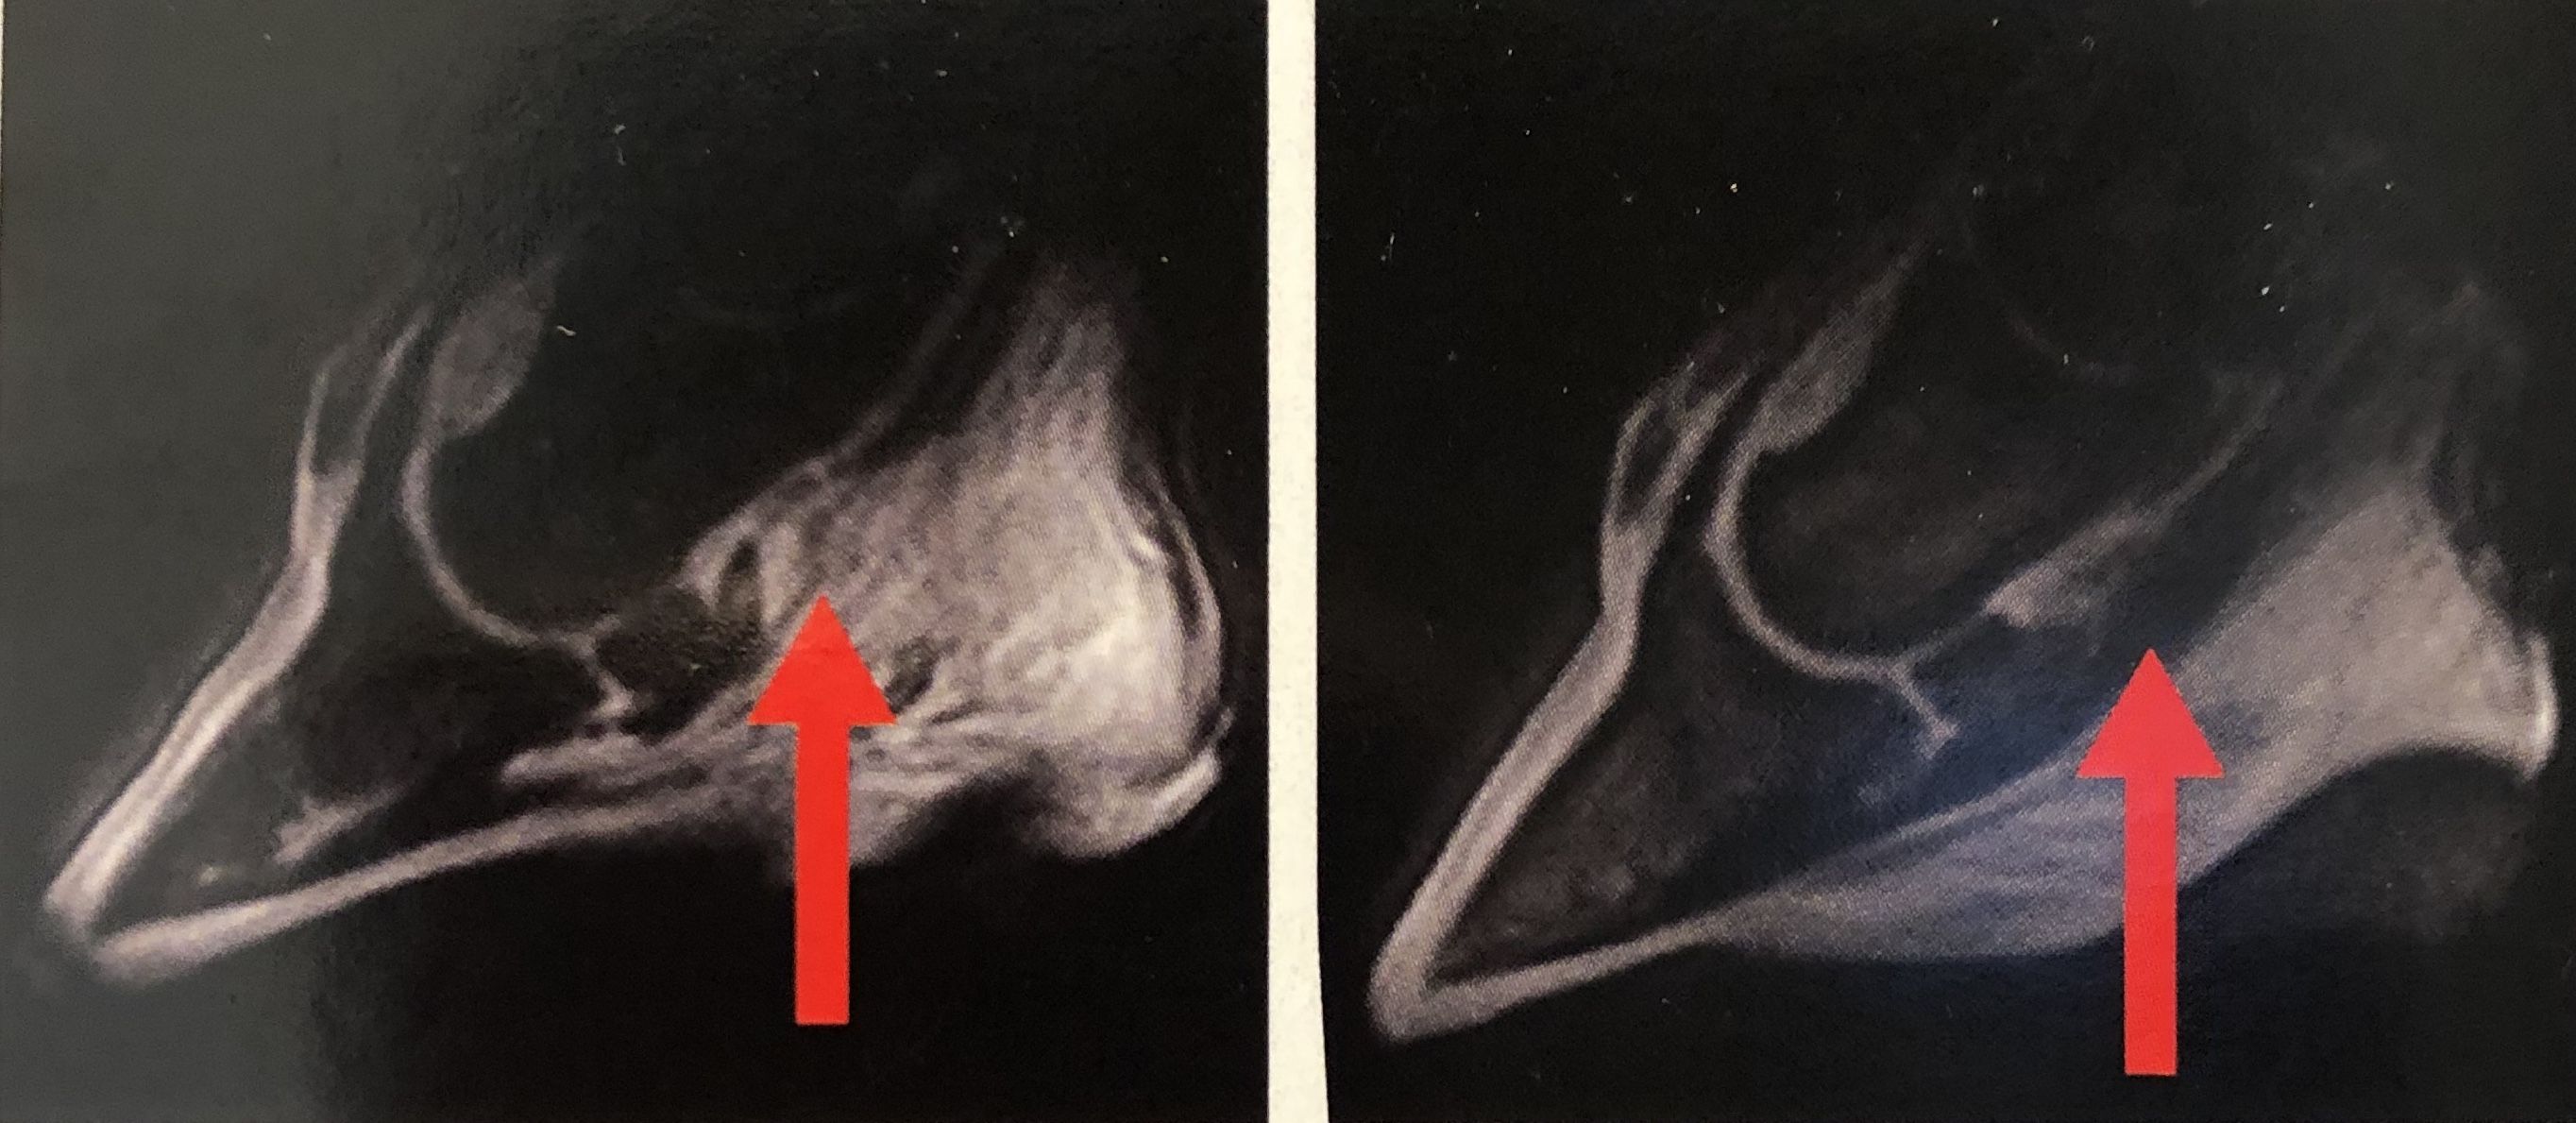

PBEC Regenerative Laser Therapy Case Study: Lameness

Patient Condition: Grand Prix level show jumper with left front lameness

Evaluation: Magnetic Resonance Imaging (MRI) showed intra-osseous fluid accumulation in the left front third metacarpal condyle.

Treatment: 20 sessions of Dr. Novoa’s SmartRLT

Result: Fluid in the third metacarpal condyle was resolved